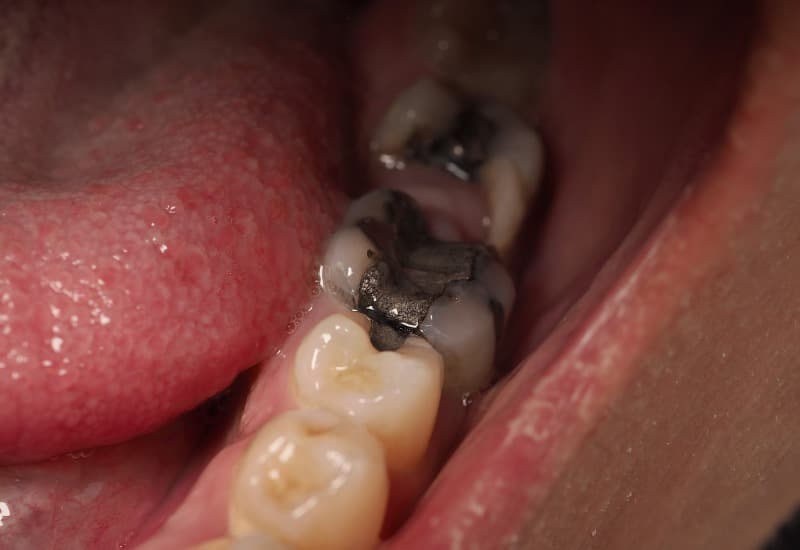

– Đau nhức dữ dội: Khi sâu răng phát triển vào các lớp trong, có thể chạm đến tủy răng, gây đau nhức dữ dội, ảnh hưởng nghiêm trọng đến khả năng ăn nhai và chất lượng cuộc sống.

Khi sâu răng phát triển vào các lớp trong, có thể chạm đến tủy răng, gây đau nhức dữ dội.